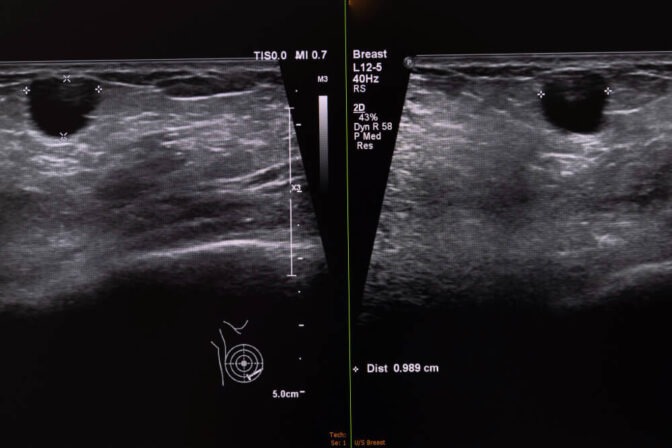

Ultrassonografia (avalia estrutura, tamanho, vascularização)